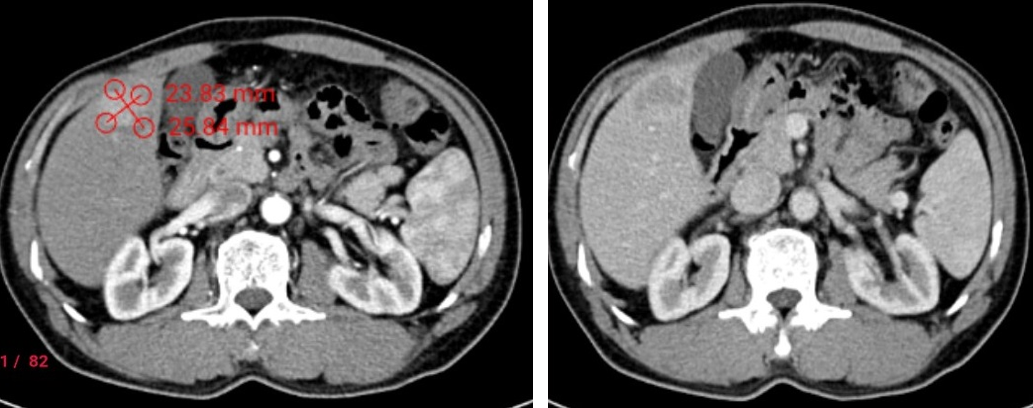

Trường hợp bệnh nhân nam 63 tuổi Ung thư gan hạ phân thùy V kích thước khoảng 30x25x23mm được phẫu thuật cắt gan hạ phân thùy V qua nội soi, sau phẫu thuật 03 ngày bệnh nhân có thể vận động đi lại, ăn uống bình thường.

Hình ảnh khối U kích thước khoảng 23x25mm ngấm thuốc mạnh thì động mạch, thải thuốc nhanh thì tĩnh mạch trên cắt lớp vi tính